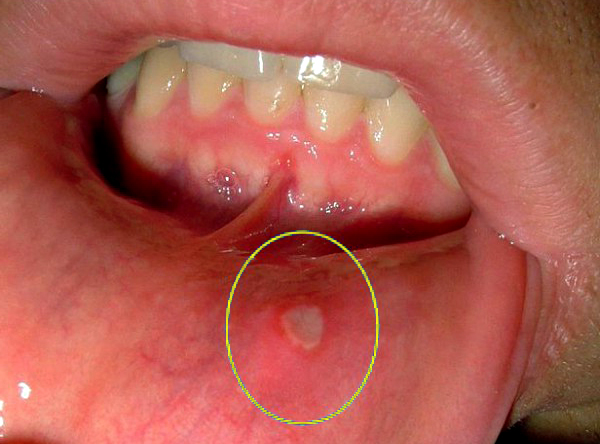

У меня стаж аналога лет 20 (от бычков и самосада, до сигар и трубки), вэйпинга - лет 5 (первые пару лет с переменным успехом), десятки мегабайт прочитанных форумов (наших и буржуйских) по сабжу. Был я и любителем клаудчейсинга, абсолютно непрерывного парения в течении дня с литрами кофе и дичайшим тремором и т.д. В свое время я также проходил (с перепугу) глотания зонда, рентген легких, УЗИ брюшной полости, кровоточащие месяцами десны, стоматит, гаймориты (пар-то горячий, и греет зубы, которые в свою очередь греют гайморовы пазухи) и пр., жрал антибиотики как витамины. Но не сцы, - будешь следовать моим правилам, можешь спокойно парить.